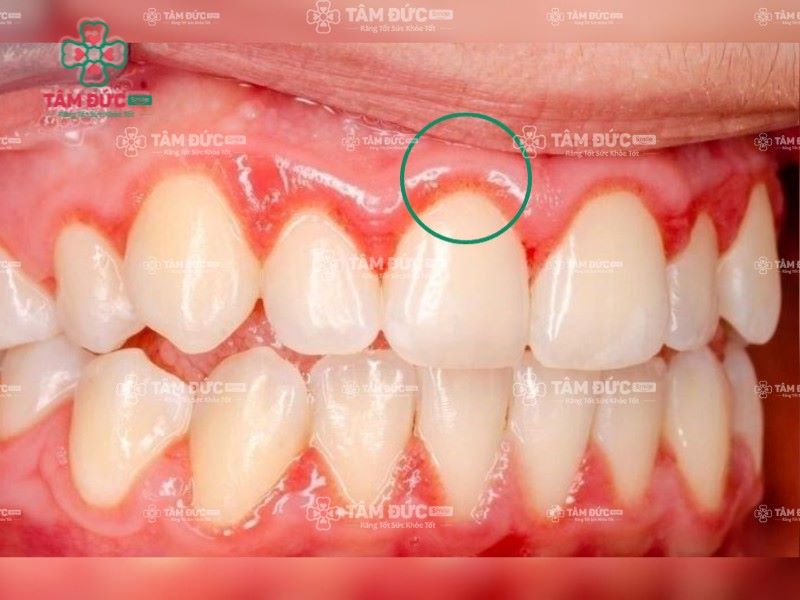

Viêm lợi là một trong những bệnh lý viêm nhiễm ở khoang miệng, làm nướu sưng đỏ và chảy máu. Tình trạng này bắt nguồn từ sự tấn công của vi khuẩn trong mảng bám, hoặc do cao răng tồn tại trong thời gian dài gây ra. Khi không được điều trị đúng cách, viêm lợi sẽ nhanh chóng tiến triển thành viêm nha chu.

Cao răng là một trong những nguyên nhân gây viêm lợi chân răng

Viêm lợi sưng đỏ nhanh chóng tiến triển thành viêm nha chu